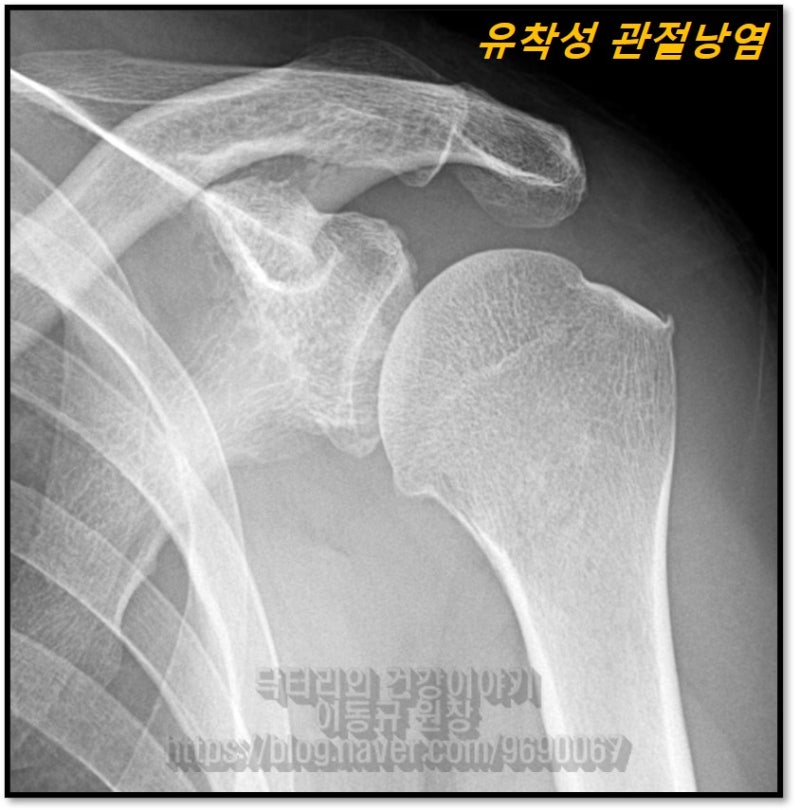

안녕하세요. 정형외과 전문의 이동규 입니다. 오늘은 치료되지 않는 오십견은 어떻게 치료해야 하는지 고민해 보겠습니다. 오십견은 어떠한 이유에서건 관절낭에 염증이 생기면서 관절낭이 유착되어 통증과 가동범위 제한을 일으키는 질환입니다. 단순 오십견일 경우는 관절낭의 염증을 제거하고 가동범위 회복하는 재활을 통해 충분히 치료 될 수 있습니다. 하지만 단순한 오십견이 아닌 다른 질환으로 인한 오십견이 발생되었다면 그 원인을 해결해야 오십견이 치료될 수 있습니다. 그 원인으로 회전근개 질환, 석회성 건염 등의 어깨 질환이 있을 수 있고 내과적으로 당뇨나 갑상선 질환이 있을 경우도 오십견이 발생될 수 있습니다. 오십견으로 치료를 했는데도 호전되지 않거나 반복되는 재발로 인해 고생하신다면 정확한 원인을 먼저 찾는 것이 순서입니다. 이번에 보여드릴 케이스는 4년동안 오십견을 진단 받고 치료를 받았으나 반복적으로 재발되고 통증으로 밤에 잠을 잘 수 없을 정도로 힘들어 하시는 분입니다. 치료는 주사치료, 충격파 치료, 도수치료 등등 안해본 것이 없으실 정도로 치료를 받았으며 타 병원에서 핌스 치료를 받았는데도 호전되지 않아서 저한테 내원한 분이었습니다.

이 환자의 경우는 극상근의 부분 손상이 치유되지 않아 반복적으로 염증이 발생되었을 것으로 판단되며 이로 인한 유착성 관절낭염(오십견)이 치료되지 않았을 것으로 사료됩니다. 환자분께 극상근의 부분 손상과 유착성 관절낭염을 같이 치료 할 수 있는 뉴핌스 치료를 하였습니다.